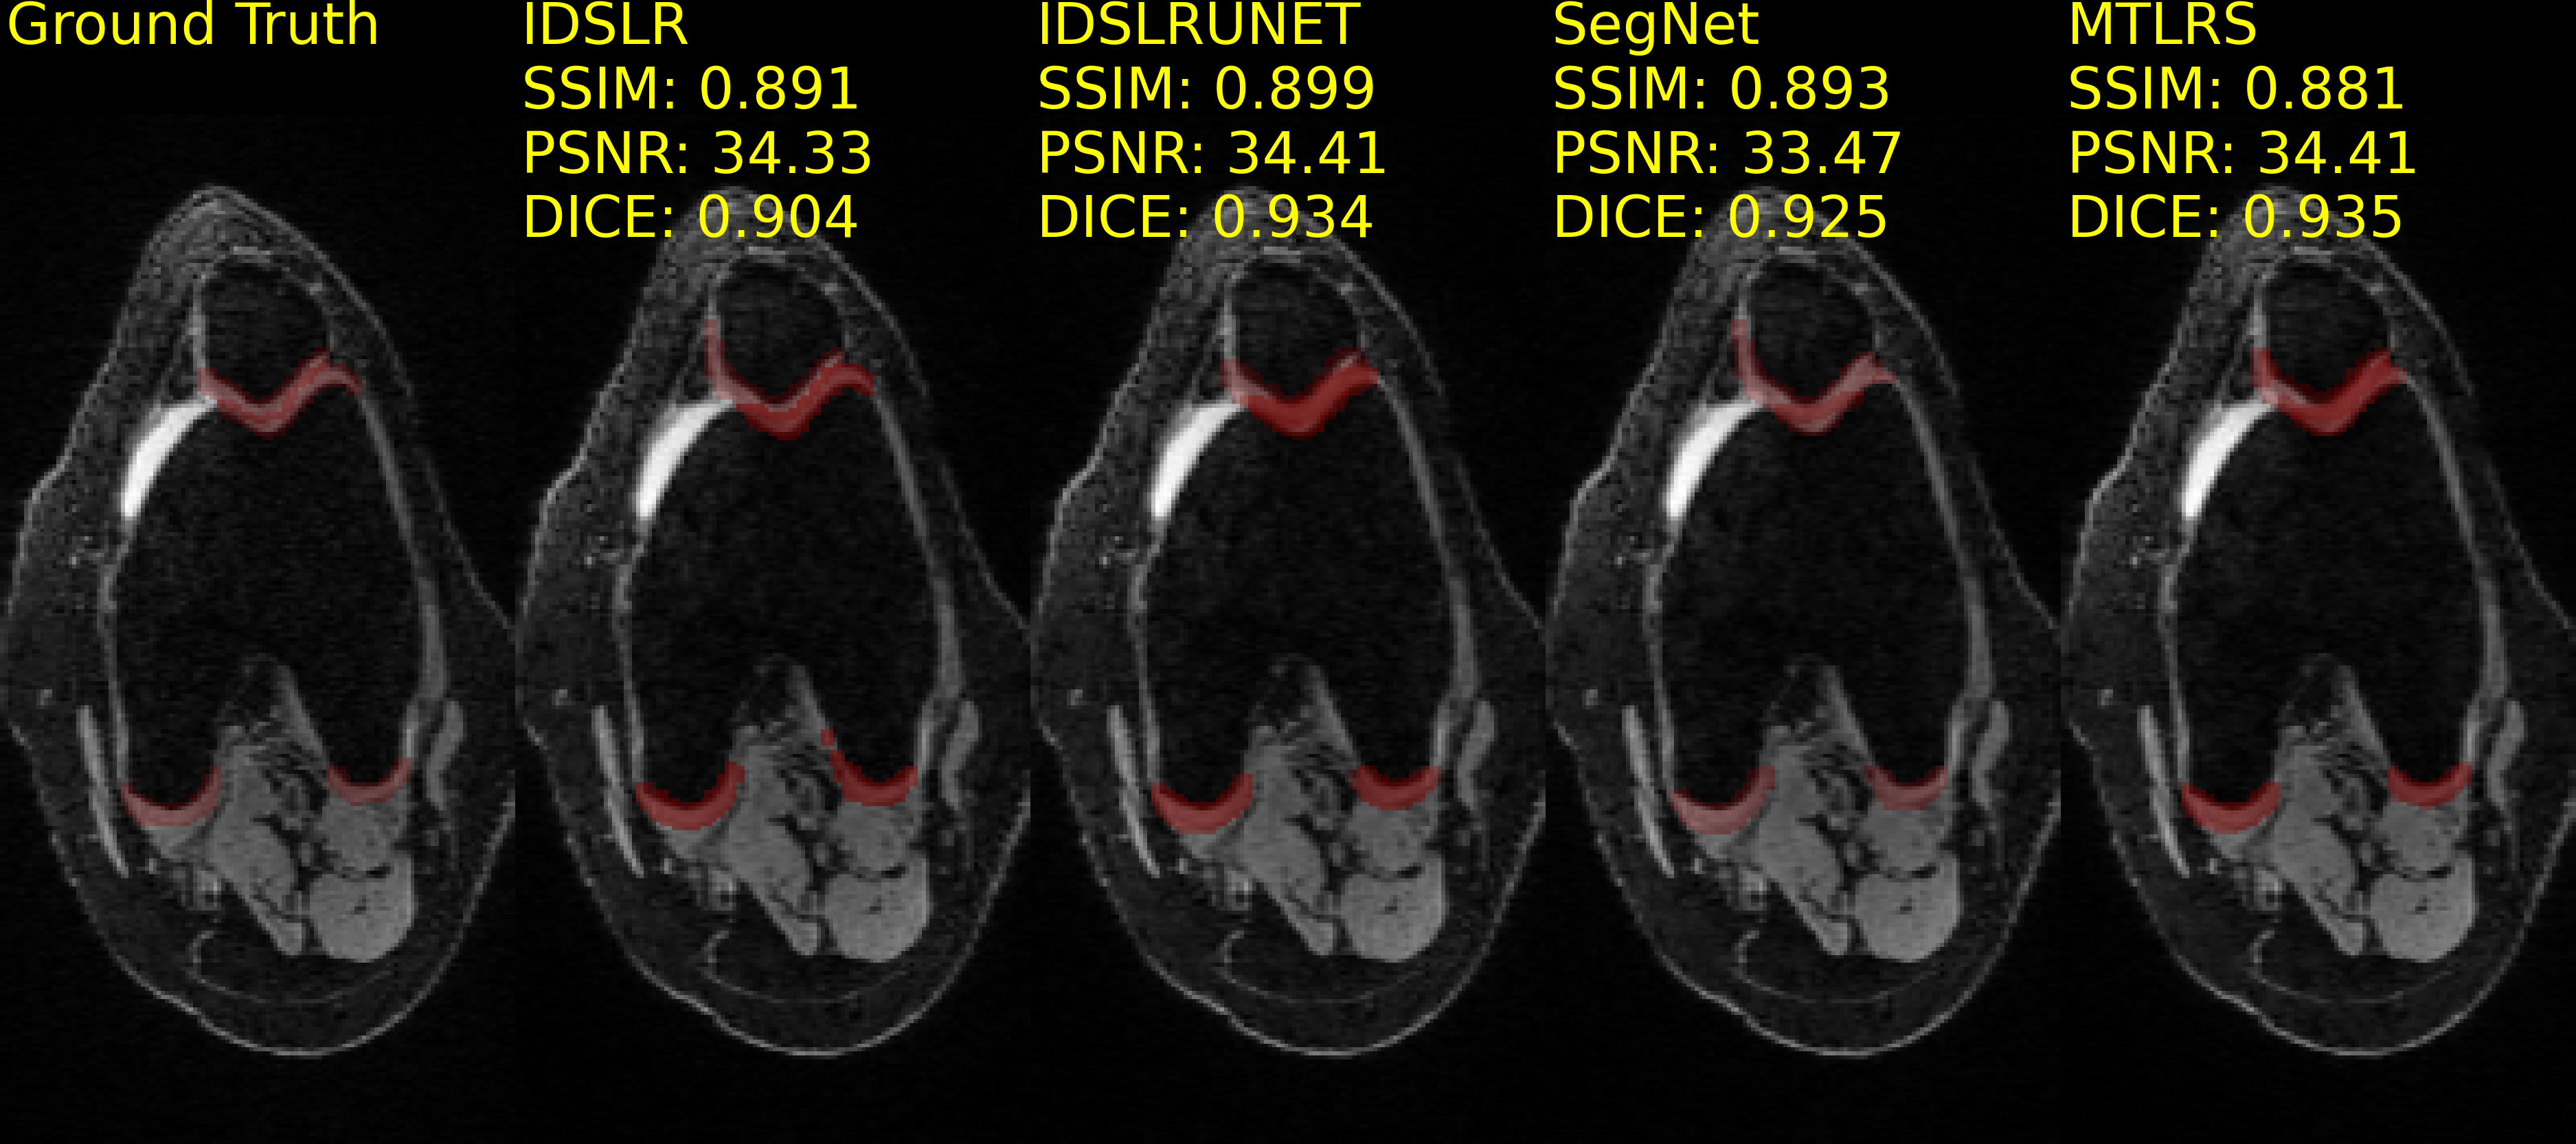

Table 7 reports the performance in MTL for joint reconstruction and segmentation models trained on the SKM-TEA dataset. The IDSLRUNET achieved the highest SSIM and PSNR scores, while the SegNet achieved the highest DICE, F1, and IOU and lowest HD95 scores. The lower F1 and IOU scores, as also observed in the performance of the segmentation-only models, may be attributed to varying patient anatomy, data acquisition, and different knee structures. Example reconstructions and segmentations when performing MTL can be found in Fig. 10.

Model SKM-TEA - Poisson 2D 4x SSIM \uparrow PSNR \uparrow DICE \uparrow F1 \uparrow HD95 \downarrow IOU \uparrow IDSLR 0.836 ±plus-or-minus\pm 0.106 30.38 ±plus-or-minus\pm 5.67 0.894 ±plus-or-minus\pm 0.127 0.256 ±plus-or-minus\pm 0.221 4.927 ±plus-or-minus\pm 2.812 0.298 ±plus-or-minus\pm 0.309 IDSLRUNET 0.842 ±plus-or-minus\pm 0.106 30.53 ±plus-or-minus\pm 5.59 0.870 ±plus-or-minus\pm 0.134 0.225 ±plus-or-minus\pm 0.194 8.724 ±plus-or-minus\pm 3.298 0.212 ±plus-or-minus\pm 0.199 MTLRS 0.832 ±plus-or-minus\pm 0.106 30.48 ±plus-or-minus\pm 5.30 0.889 ±plus-or-minus\pm 0.118 0.247 ±plus-or-minus\pm 0.203 7.594 ±plus-or-minus\pm 3.673 0.218 ±plus-or-minus\pm 0.194 SegNet 0.840 ±plus-or-minus\pm 0.107 29.95 ±plus-or-minus\pm 5.12 0.915 ±plus-or-minus\pm 0.114 0.270 ±plus-or-minus\pm 0.284 3.002 ±plus-or-minus\pm 1.449 0.290 ±plus-or-minus\pm 0.349

Refer to caption

Figure 10: Reconstructions and segmentations on the Stanford Knee MRI with Multi-Task Evaluation (SKM-TEA) dataset, undersampled with a Poisson disc distribution 2D pattern for 4x acceleration. First image shows the Ground Truth image and segmentation labels. SSIM, PSNR, and DICE scores are reported for each method and computed against the Ground Truth image and segmentation labels. Methods are sorted alphabetically. Images are interpolated for visualisation purposes from 416×8041680416\times 80 to 256×128256128256\times 128.